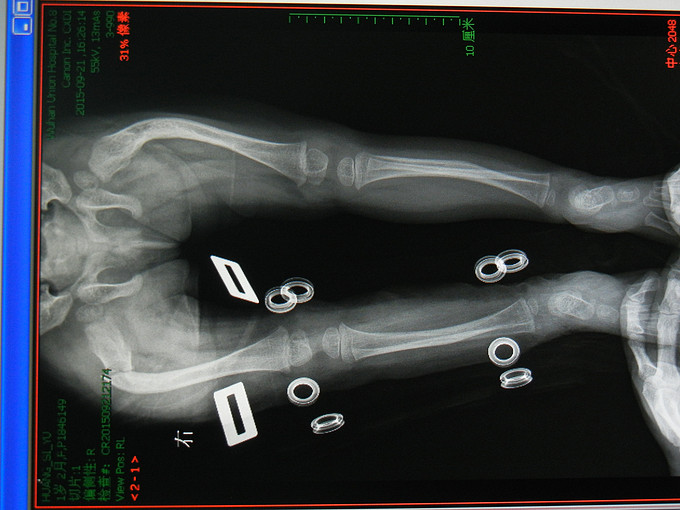

患儿女,1岁。因“外伤后右大腿肿痛伴活动受限一天”入院。现病史:患儿家属代诉,昨日下午7时许,患者不慎摔伤右大腿,当即感觉伤处肿胀、疼痛、活动受限,无恶心呕吐,无头痛胸腹痛,无休克和昏迷。在当地医院给予简单包扎,并拍片提示右股骨骨折,门诊以“右股骨骨折、成骨不全”收入院。起病以来患者一般情况可。 手术史:出生后5天曾在当地脑科医院行头颅手术。

查体:生命体征平稳,心肺腹体检未见明显异常。专科情况:右大腿明显肿胀,压痛,活动受限。 辅助检查:拍片提示:右股骨骨折。

诊断:右股骨骨折,成骨不全。 行手术治疗。